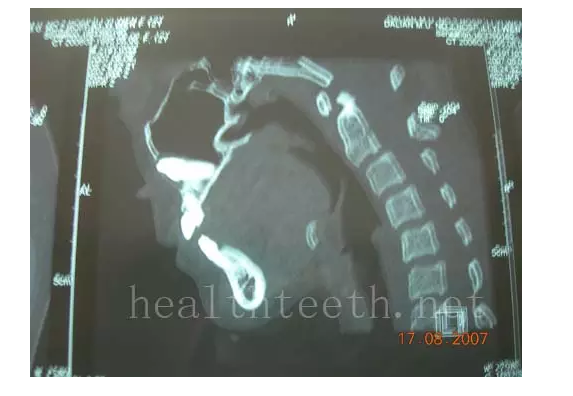

2、埋伏牙

左上乳3滯留,恒3未見萌出,曲面斷層片顯示牙齒埋伏

通過CT片確定埋伏牙齒具體的位置,顯示距離左側(cè)上頜竇很近,偏唇側(cè),這為手術(shù)定位提供了方便

手術(shù)中切斷、完整拔出,未損傷上頜竇

其他埋伏牙